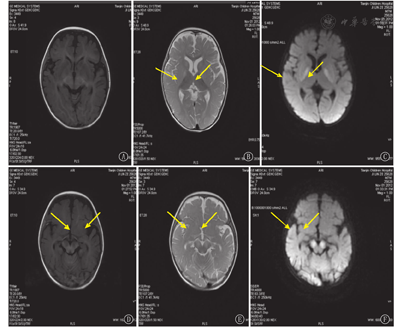

例1、2、3、4头颅MRI提示双侧苍白球对称性T2加权像(T2WI)及液体衰减反转恢复(FLAIR)序列高信号,例1伴中脑大脑脚对称性长T1、长T2及FLAIR序列高信号(图1)。例5、6、8、9头颅MRI提示脑室、脑外间隙增宽。例7头颅MRI提示左颞叶皮质区软化灶。

注:T1WI:T1加权像;T2WI:T2加权像;FLAIR:液体衰减反转恢复 T1WI:T1 weighing imaging;T2WI:T2 weighing imaging;FLAIR:fluid attented inversion recovery